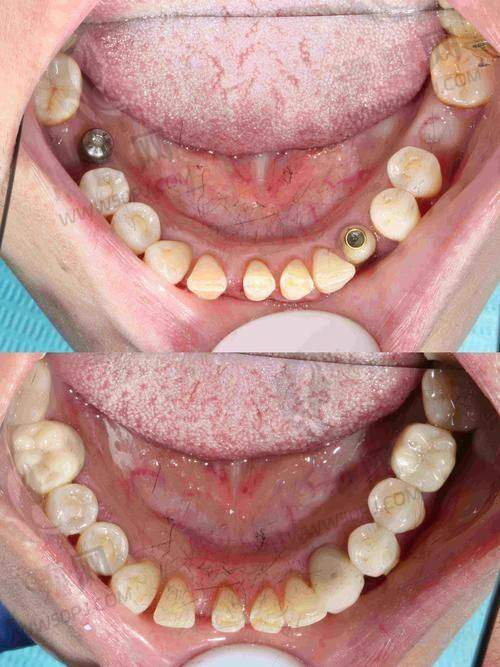

看点解读: 从装修到服务都透着“艺术试验场”风格,主打微创微痛种植、即刻负重等硬核治疗项目。适合不想长期等待、恐惧拔牙者,且支持部分多次服务。